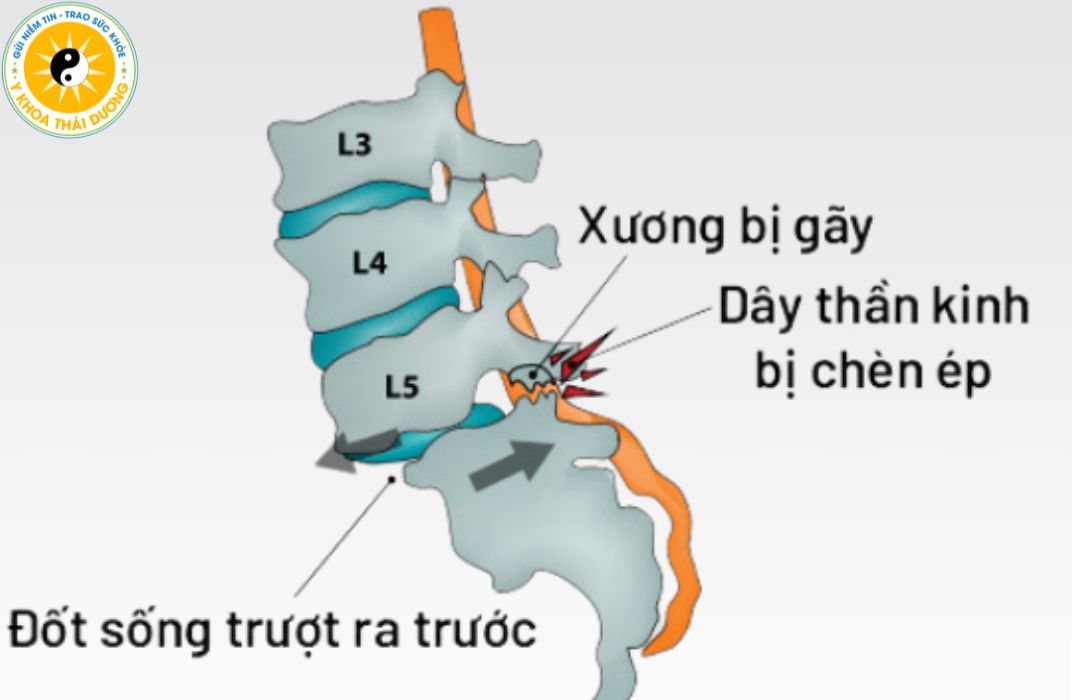

Trượt đốt sống: Nhận biết và điều trị phục hồi đúng cách

Trượt đốt sống là một trong những bệnh lý cột sống phổ biến nhưng thường...